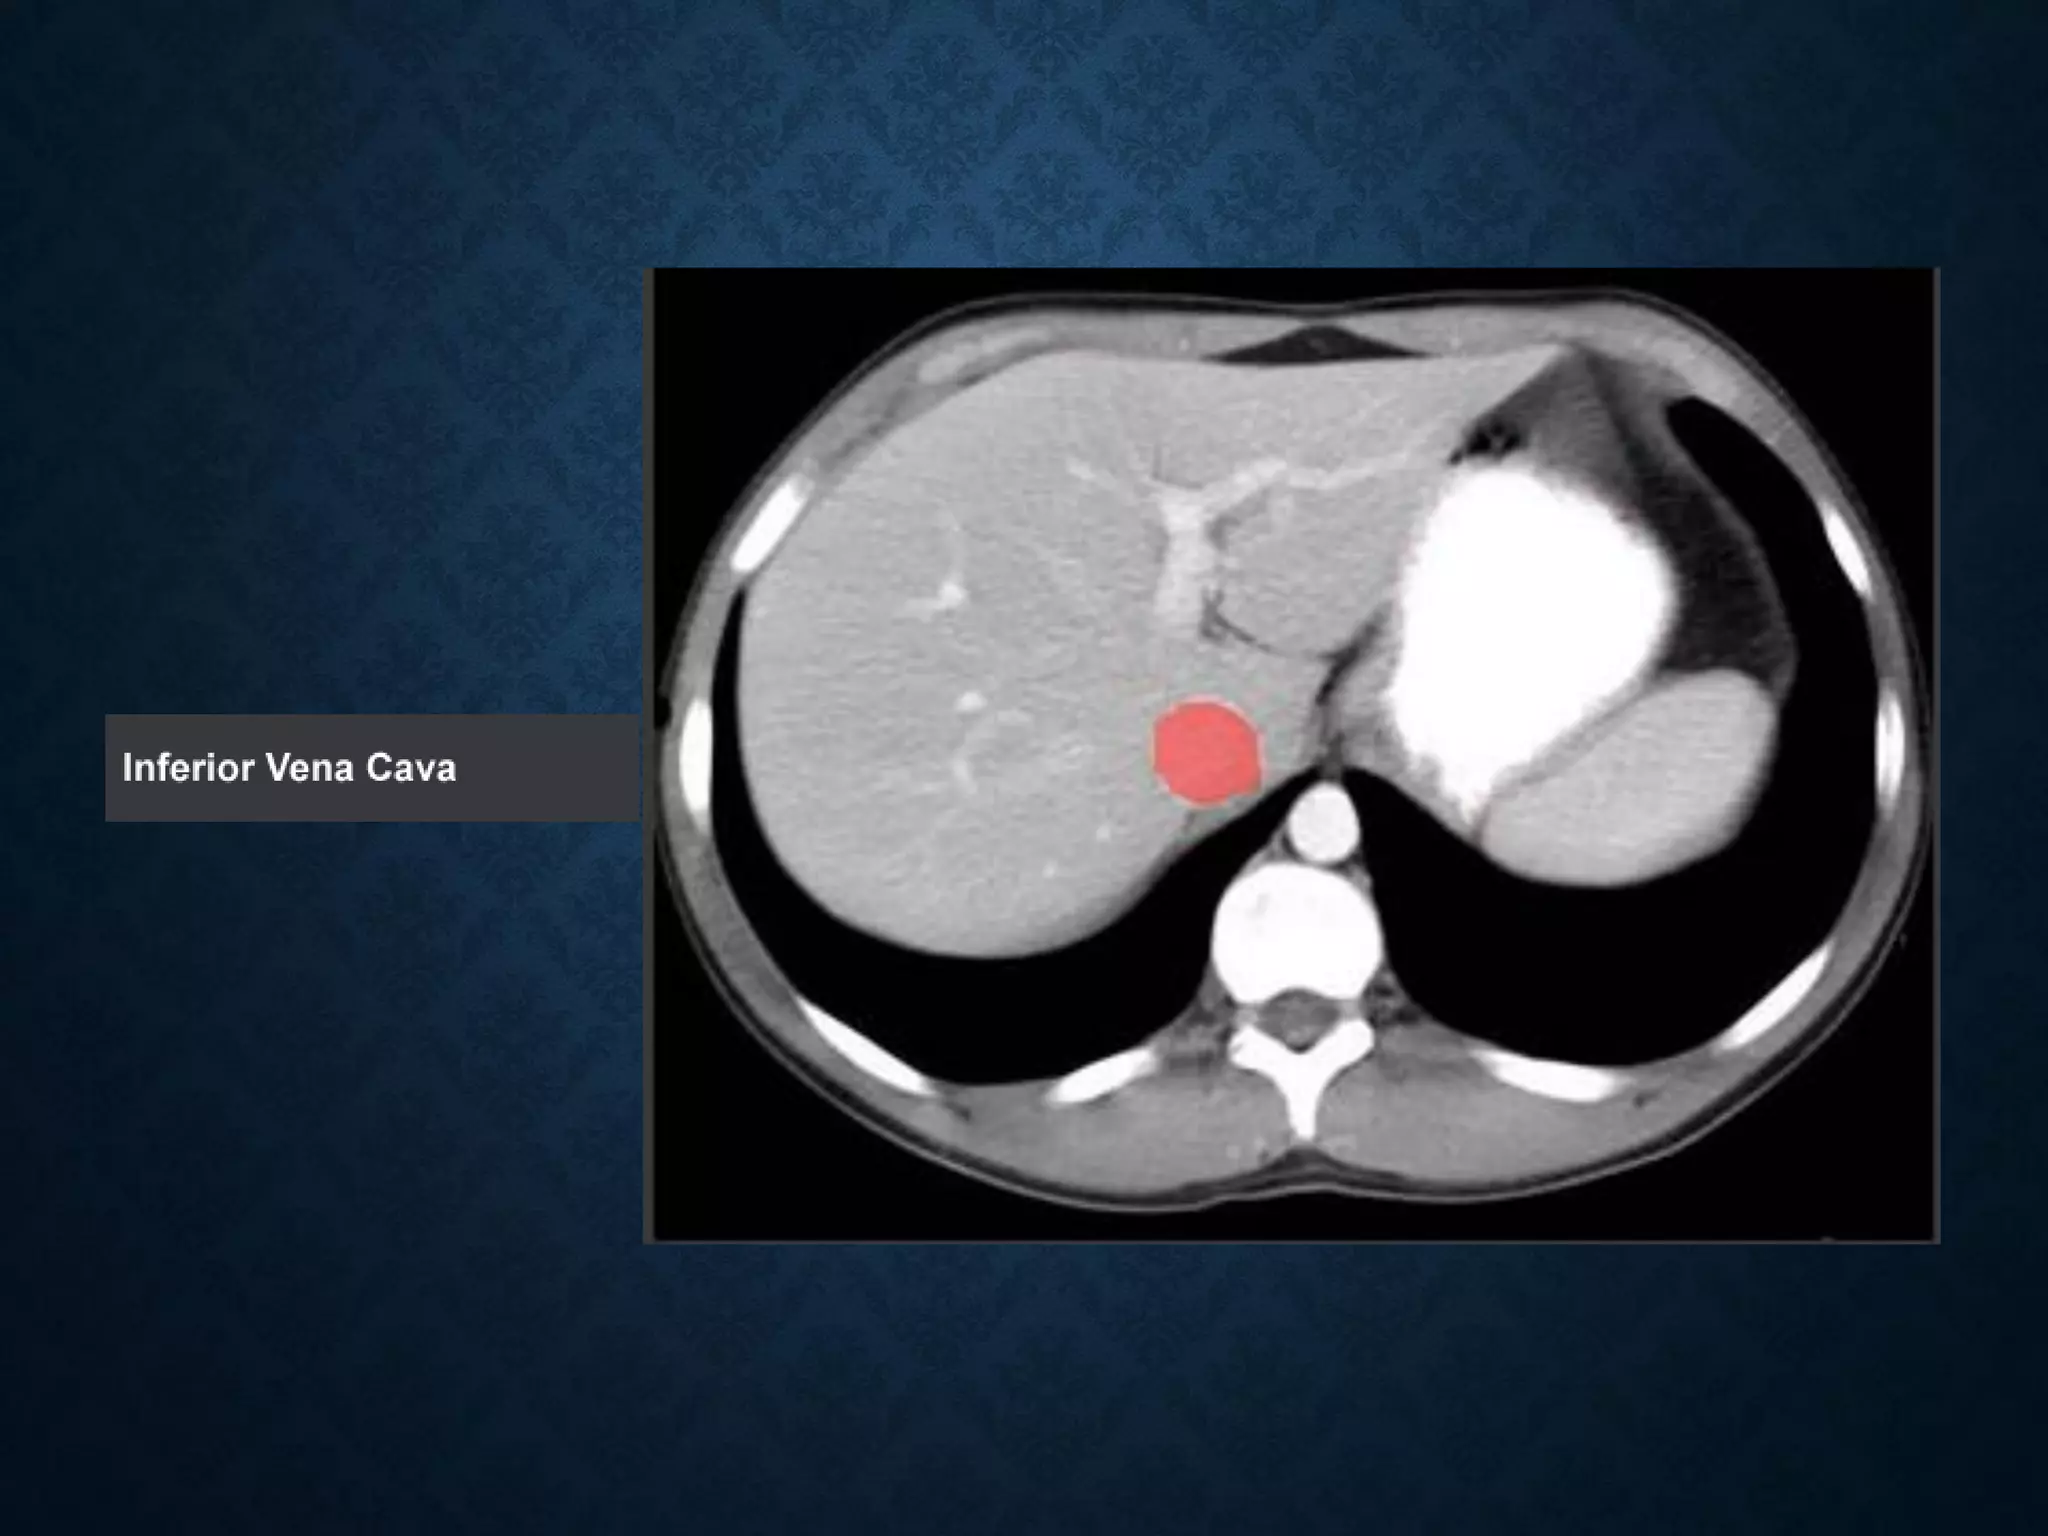

IVC

• Note that the bifurcation (union) of the inferior vena cava is at L5and

therefore below that of the bifurcation of the aorta)